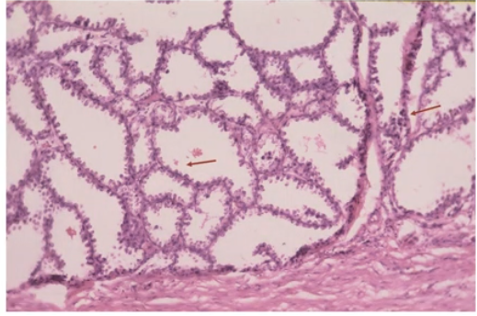

HISTOPATHOLOGY

Fig shows an endoscopic biopsy from a 54 year old individual. Identify the anatomical part of the intestine. What is the pathology. With what clinical symptoms do these patients present? (see surface epithelium)